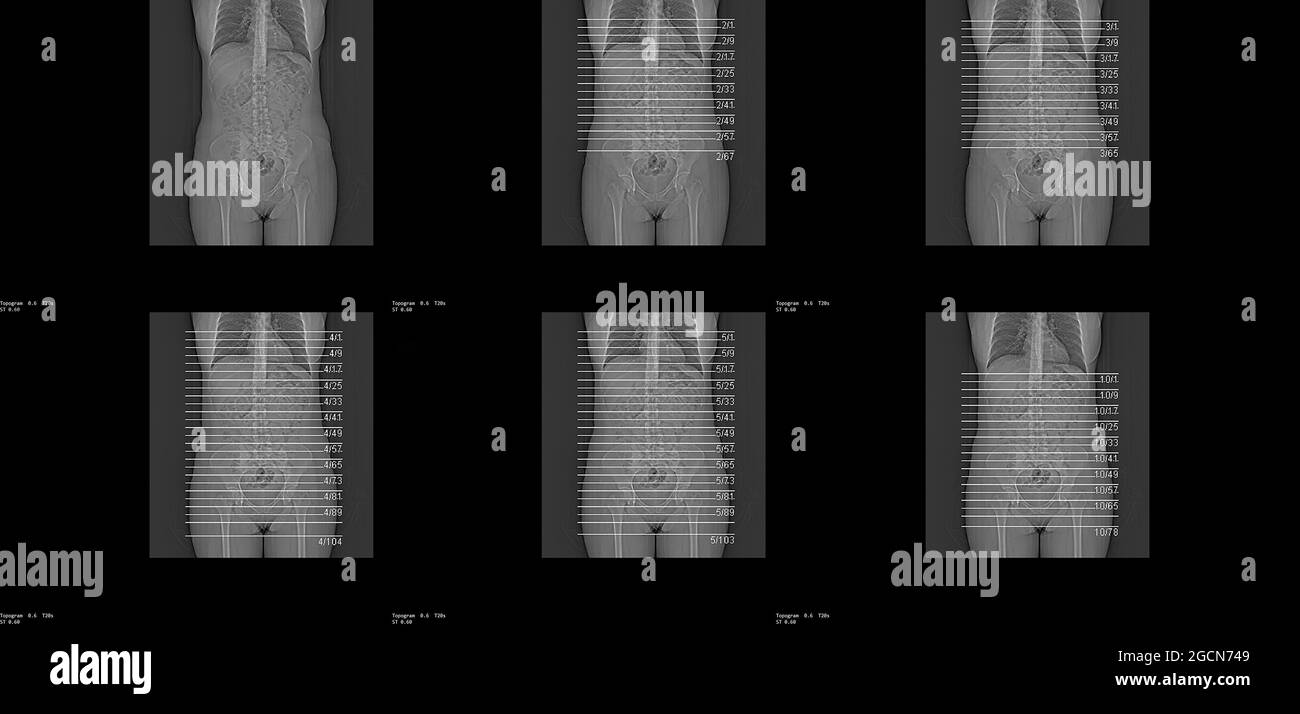

RF2GCN749–La vista scout (topogramma) per una TC dell'addome e del bacino con contrasto endovenoso. Immagini di riferimento per l'acquisizione di una serie TC assiale.